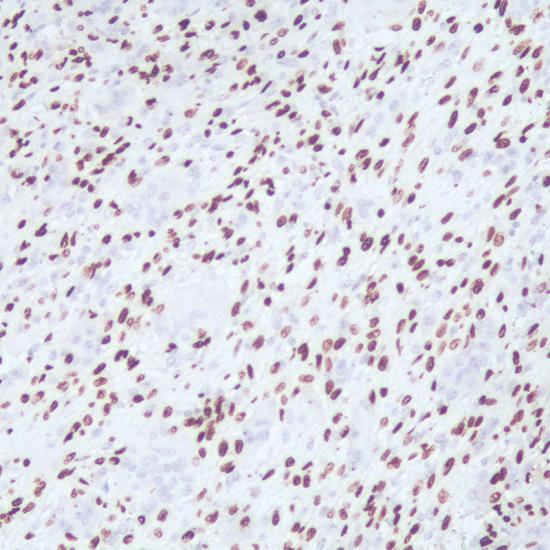

H3.3G34W抗體試劑(免疫組織化學(xué)法) 閩廈械備20220001號

• 陽性部位:

細(xì)胞核

• 陽性對照:

骨巨細(xì)胞瘤

骨巨細(xì)胞瘤、骨囊腫、軟骨母細(xì)胞瘤和骨肉瘤等腫瘤存在形態(tài)學(xué)上的相似,使得骨巨細(xì)胞瘤的診斷存在很大的挑戰(zhàn)性。H3.3 G34W突變抗體是診斷骨巨細(xì)胞瘤高度靈敏和特異的標(biāo)志物, 有助于與其它形態(tài)相似的骨腫瘤進(jìn)行鑒別診斷。